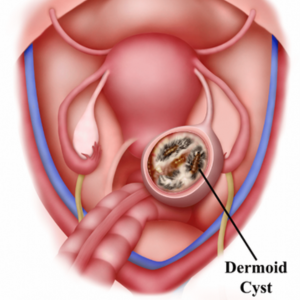

Dermoid Cyst